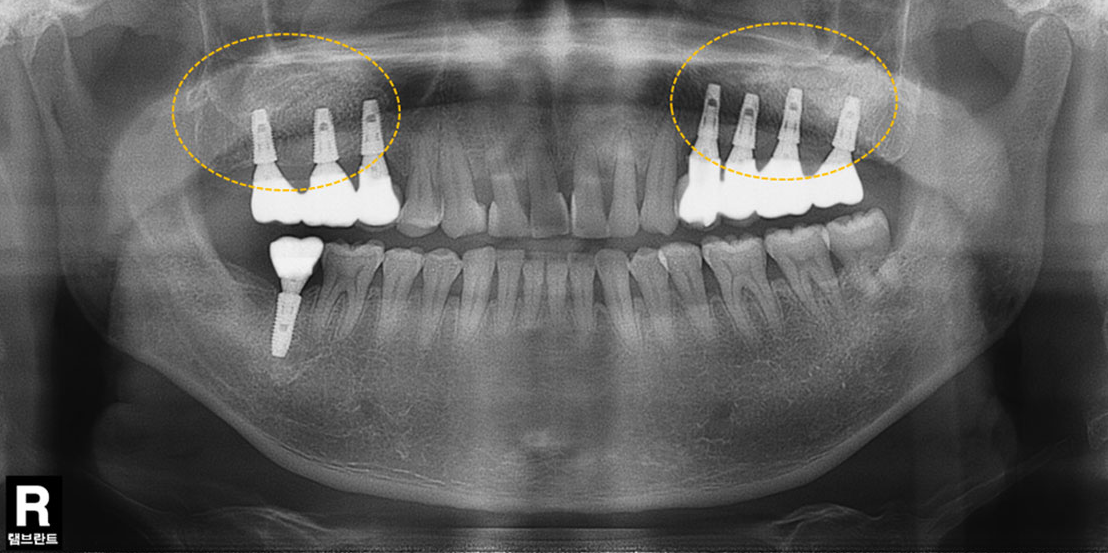

윗턱뼈 공기주머니에 뼈이식

치료 전

치료 후